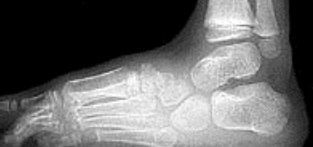

| What is this? What foot type is this visible in? | Sinus tarsi/bullet hole sign. Pes cavo-varus |